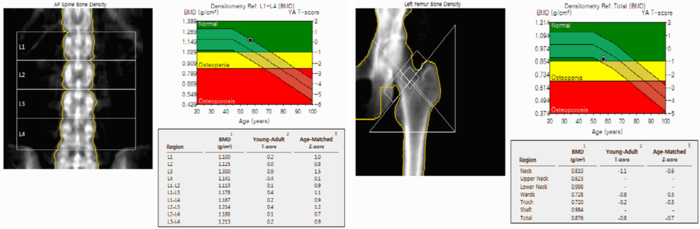

- 골절 위험 조기 예측: DXA(이중에너지 X선 흡수계측)로 요추·대퇴부 골밀도를 측정해 T-score를 얻습니다.

검사 결과 읽는 법(기본)

- T-score ≥ –1.0 : 정상

- –2.5 < T-score < –1.0 : 골감소증(생활습관 개선·칼슘 1,200 mg 권장)

- T-score ≤ –2.5 : 골다공증(약물·정기 추적검사 필요)